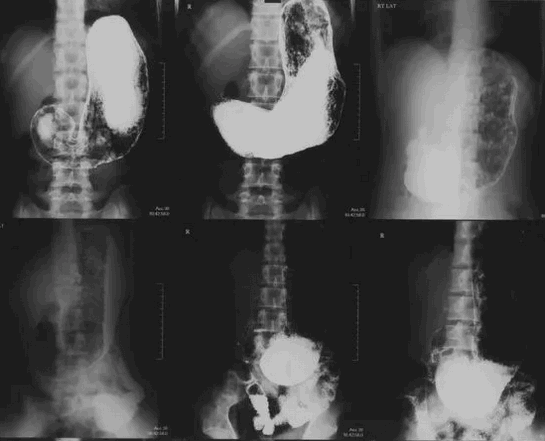

Рентгеноскопия желудка – это диагностическое исследование, представляющее собой неинвазивную методику, которая даёт возможность исследовать форму, размеры, положение пищевода, желудка и 12-перстной кишки, а также выявить их анатомические особенности и патологические изменения.

Рентгеноскопия пищевода, желудка и 12-перстной кишки позволяет обнаружить и дифференцировать следующие патологические процессы:

- нарушение продвижения контрастной массы по пищеводу, желудку и 12-перстной кишке (нарушение моторики ЖКТ);

- воспалительные изменения пищевода, желудка и 12-перстной кишки: эзофагит, гастрит, дуоденит; ;

- заболевания пищевода: ахалазия пищевода, варикозное расширение вен пищевода, грыжа пищеводного отверстия диафрагмы, дивертикулы пищевода и другие;

- деформацию 12-перстной кишки и ее отделов за счет рубцевания, стеноза, сдавления извне;

- новообразования в стенках желудка и 12-перстной кишки и др.

Желудок – это орган брюшной полости с полой структурой. Для выполнения объективного рентгенологического исследования используется дополнительное контрастирование водным раствором сульфата бария в количестве 250-300 мл, который безвреден для организма пациента, не всасывается в желудочно-кишечном тракте и выводится в неизмененном виде.

Иногда при необходимости исследования внутренней поверхности желудка и антрального отдела применяется двойное контрастирование.

При проведении исследования, которое длится 30-40 минут, врач обязательно оценивает прохождение контрастной массы по пищеводу, желудку и 12-перстной кишке, отмечает изменения и производит рентгеновские снимки. Они обрабатываются в конце исследования и дают возможность рентгенологу правильно оценить состояние исследуемых органов и поставить диагноз.

Исследование обычно проводится в вертикальном положении. Также выполняем рентгеноскопию в положении Тренделенбурга. Так называется положение пациента на операционном столе, когда тазовые органы находятся чуть выше головы.